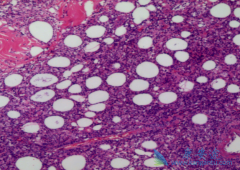

弥漫性大B细胞淋巴瘤 是最常见的非霍奇金淋巴瘤,在我国,其占所有恶性淋巴瘤的比例超过40%。它多发于中老年人,40~50岁多见。在临床上,患者常表现为迅速增大的淋巴结,10%~15%患者有骨髓侵犯,40%~50%患者有淋巴结外病变,患者常出现发热、盗汗、 ...

非霍奇金淋巴瘤 诊断必须依靠病理确诊。同时根据组织细胞形态特点,结合免疫表型和细胞遗传学特征可以明确病理类型,对指导个体化治疗用药和判断预后有益。发病率高并有代表性的非霍奇金淋巴瘤:1.B细胞类型。弥漫大B细胞淋巴瘤、滤泡淋巴瘤、套细胞淋 ...

由于 非霍奇金淋巴瘤 是一组淋巴造血系统恶性肿瘤的总称,所以临床表现既有一定的共同特点,同时按照不同的病理类型、受侵犯的部位和范围又存在很大的差异。病变虽然发于淋巴结,但依据淋巴系统的分布特点,使得非霍奇金淋巴瘤基本属于全身性疾病。1.局 ...

非霍奇金淋巴瘤 ,约占所有淋巴瘤80%左右,其中有三分之二原发于淋巴结,三分之一原发于淋巴结外器官或组织,如消化和呼吸道、肺、皮肤、涎腺、甲状腺及中枢神经系统等。有专家解释称淋巴瘤是一种不同于其他癌症的“液体癌”,淋巴瘤细胞可以随着淋巴系 ...